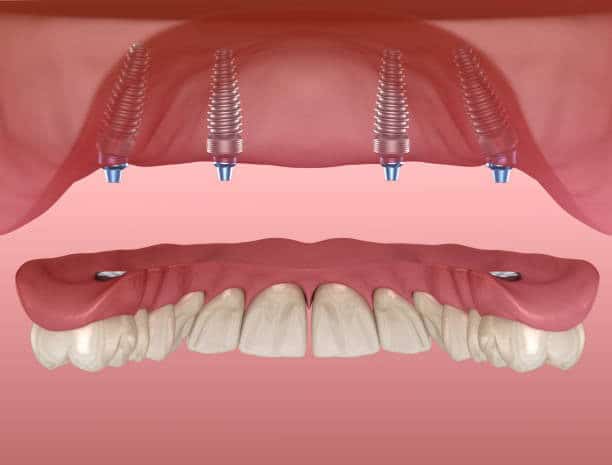

All-on-4 është një trajtim i avancuar dentar që përdor katër implante titani të vendosura strategjikisht për të mbështetur një hark të plotë dhëmbësh, qoftë në nofullën e sipërme, në nofullën e poshtme, ose në të dyja.

Ndryshe nga protezat tradicionale që vendosen mbi mishrat e dhëmbëve dhe mund të lëvizin ose shkaktojnë dhimbje, implantet All-on-4 janë të ngulitura në mënyrë të përhershme në kockën e nofullës. Rezultati është një protezë fikse që duket, ndihet dhe funksionon saktësisht si dhëmbët natyralë.

Katër implantet janë pozicionuar në kënde strategjike për të maksimizuar kontaktin me kockën e nofullës. Kjo do të thotë se në shumicën e rasteve nuk nevojitet transplant kockor, madje edhe për pacientët me humbjeje të kockës.

Procedura kryhet nën anestezi lokale për rehati maksimale. Katër implante titani vendosen strategjikisht në kockën e nofullës në kënde specifike për të maksimizuar stabilitetin dhe për të mbështetur restaurimin e plotë të harkut.